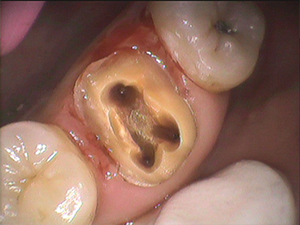

歯の神経の入口は奥歯の場合

通常3つしかない

と教科書では教えられています。

しかし、実際に私が全国からお越し下さる患者さんのお口の中を診せて頂き

根管治療(歯の神経治療)をしていく中では

歯の神経の入口は4つ、5つ目の神経

のある方がいらっしゃいます。

これは特に珍しいケースではなく、吉本歯科医院で来院される患者様の10人のうち5人の割合でいらっしゃいます。

4つ目の神経の入口を見つける時に

役に立つのが、マイクロスコープ(手術用顕微鏡)です。

肉眼では見えないものが

マイクロスコープ(手術用顕微鏡)を使うことによって

よく見えます。